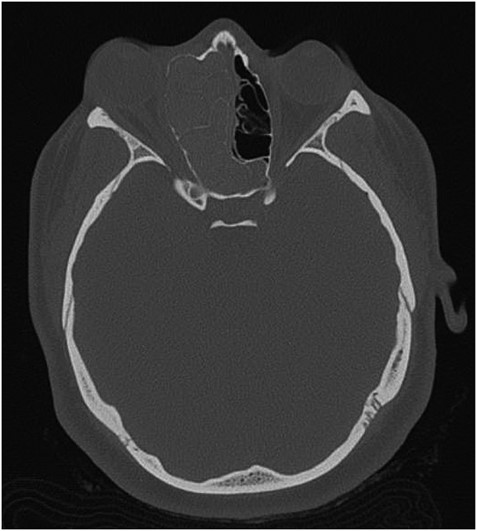

The results of the CT indicated complete opacification of the frontal, ethmoidal, sphenoidal and maxillary sinus on the right side with hyper-dense intraluminal soft tissue filling the sinus cavities. Significant widening of the ostiomeatal complex was observed (Fig. 1). Soft tissue from the right maxillary sinus extended into the right side of the nasal cavity. Extensive changes in the right ethmoidal labyrinth were also discovered. The intact lamella of the middle turbinate and lamella of the bulla ethmoidalis extended further laterally when compared to the left side, and lamina papyracea was protruding into the orbit (Figs 1 and 2). Options were discussed and endoscopic CT guided surgery was recommended.

Axial CT image indicating widening of the ostiomeatal complex with malformation of the right ethmoid.

AFS is a known risk factor for development of nasal polyps [5, 6]. Incidences of AFS causing unilateral proptosis have also been described in the literature [7, 8]. The findings from the current CT, however, indicate a unique developmental process. When compared to the patient’s left side, the extent is easily seen (Fig. 3). In consideration of the preservation of the ethmoid architecture along with the patient’s age, it appears that due to the severity and duration of the polyposis and AFS, the ethmoidal labyrinth malformed while still in development. Contrastingly, in cases of several nasal polyposis, including those with ocular involvement, bone erosion and destruction are most frequently seen with respect to changes in bone anatomy [9]. Chronic remodeling of the ethmoid bone has been described in venous malformations [10], however, cases of nasal polyps leading to bone malformation are significantly underrepresented in the literature. CT imaging proved the most valuable diagnostic tool in examining the extent of the proptosis secondary to polyposis, as well as describing the changes in the ethmoid labyrinth structure. Surgical approach proved effective in reducing the patient’s symptoms, as well as confirming the etiology of the unilateral proptosis.